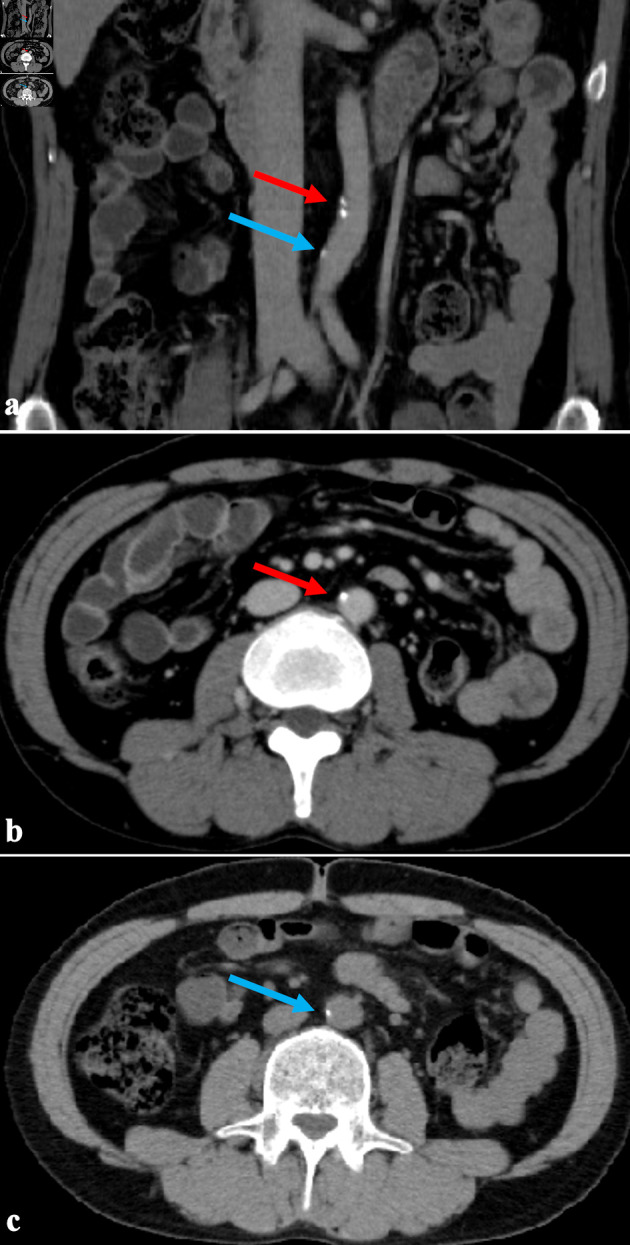

Vascular calcification is common in dialysis patients and is severely associated with cardiovascular morbidity and mortality. They have mineral metabolism disorders, which are considered to promote vascular calcification. In addition, hypertension and malnutrition, both prevalent in dialysis patients, are also considered risk factors contributing to vascular calcification. Our clinic has implemented extended-hours hemodialysis without dietary restrictions to solve the problems of hypertension and malnutrition in dialysis patients. We report a case where aortic calcification was slight despite 34 years of long-term dialysis. He underwent his first computed tomography (CT) scan of the chest and abdomen 29 years after initiating hemodialysis to evaluate his kidney transplant. The abdominal aortic calcification index 29 years after initiating dialysis was low at 5.8%, and even after 5 years, it was only 6.7%. The coronary artery calcification score was moderate at 214.0, but the degree of vascular calcification appeared milder than in conventional dialysis patients. His dialysis modality is unique. He began extended-hours hemodialysis without dietary restrictions 1.5 years after his transfer to our clinic, extending his dialysis time to 6 h. He gradually increased it to 10 h, and the dietary restriction was significantly relaxed. Moreover, he has been undergoing this treatment for about 26 years. His muscle mass increased, and his nutritional status remained adequate. The mean serum phosphorus and calcium levels were within the normal range (5.4 ± 0.5 mg/dL and 8.8 ± 0.3 mg/dL), and the calcium-based phosphate binder was successfully reduced and eventually discontinued. Furthermore, the blood pressure normalized without the use of antihypertensive medications. These may have removed some of the risk factors for vascular calcification. Recent studies suggest that extended-hours hemodialysis without dietary restrictions significantly lowers calciprotein particle levels, a risk factor for vascular calcification, compared to conventional dialysis. In conclusion, extended-hours hemodialysis without dietary restrictions may reduce the risk of vascular calcification by improving control of malnutrition, hypertension, and mineral metabolism.